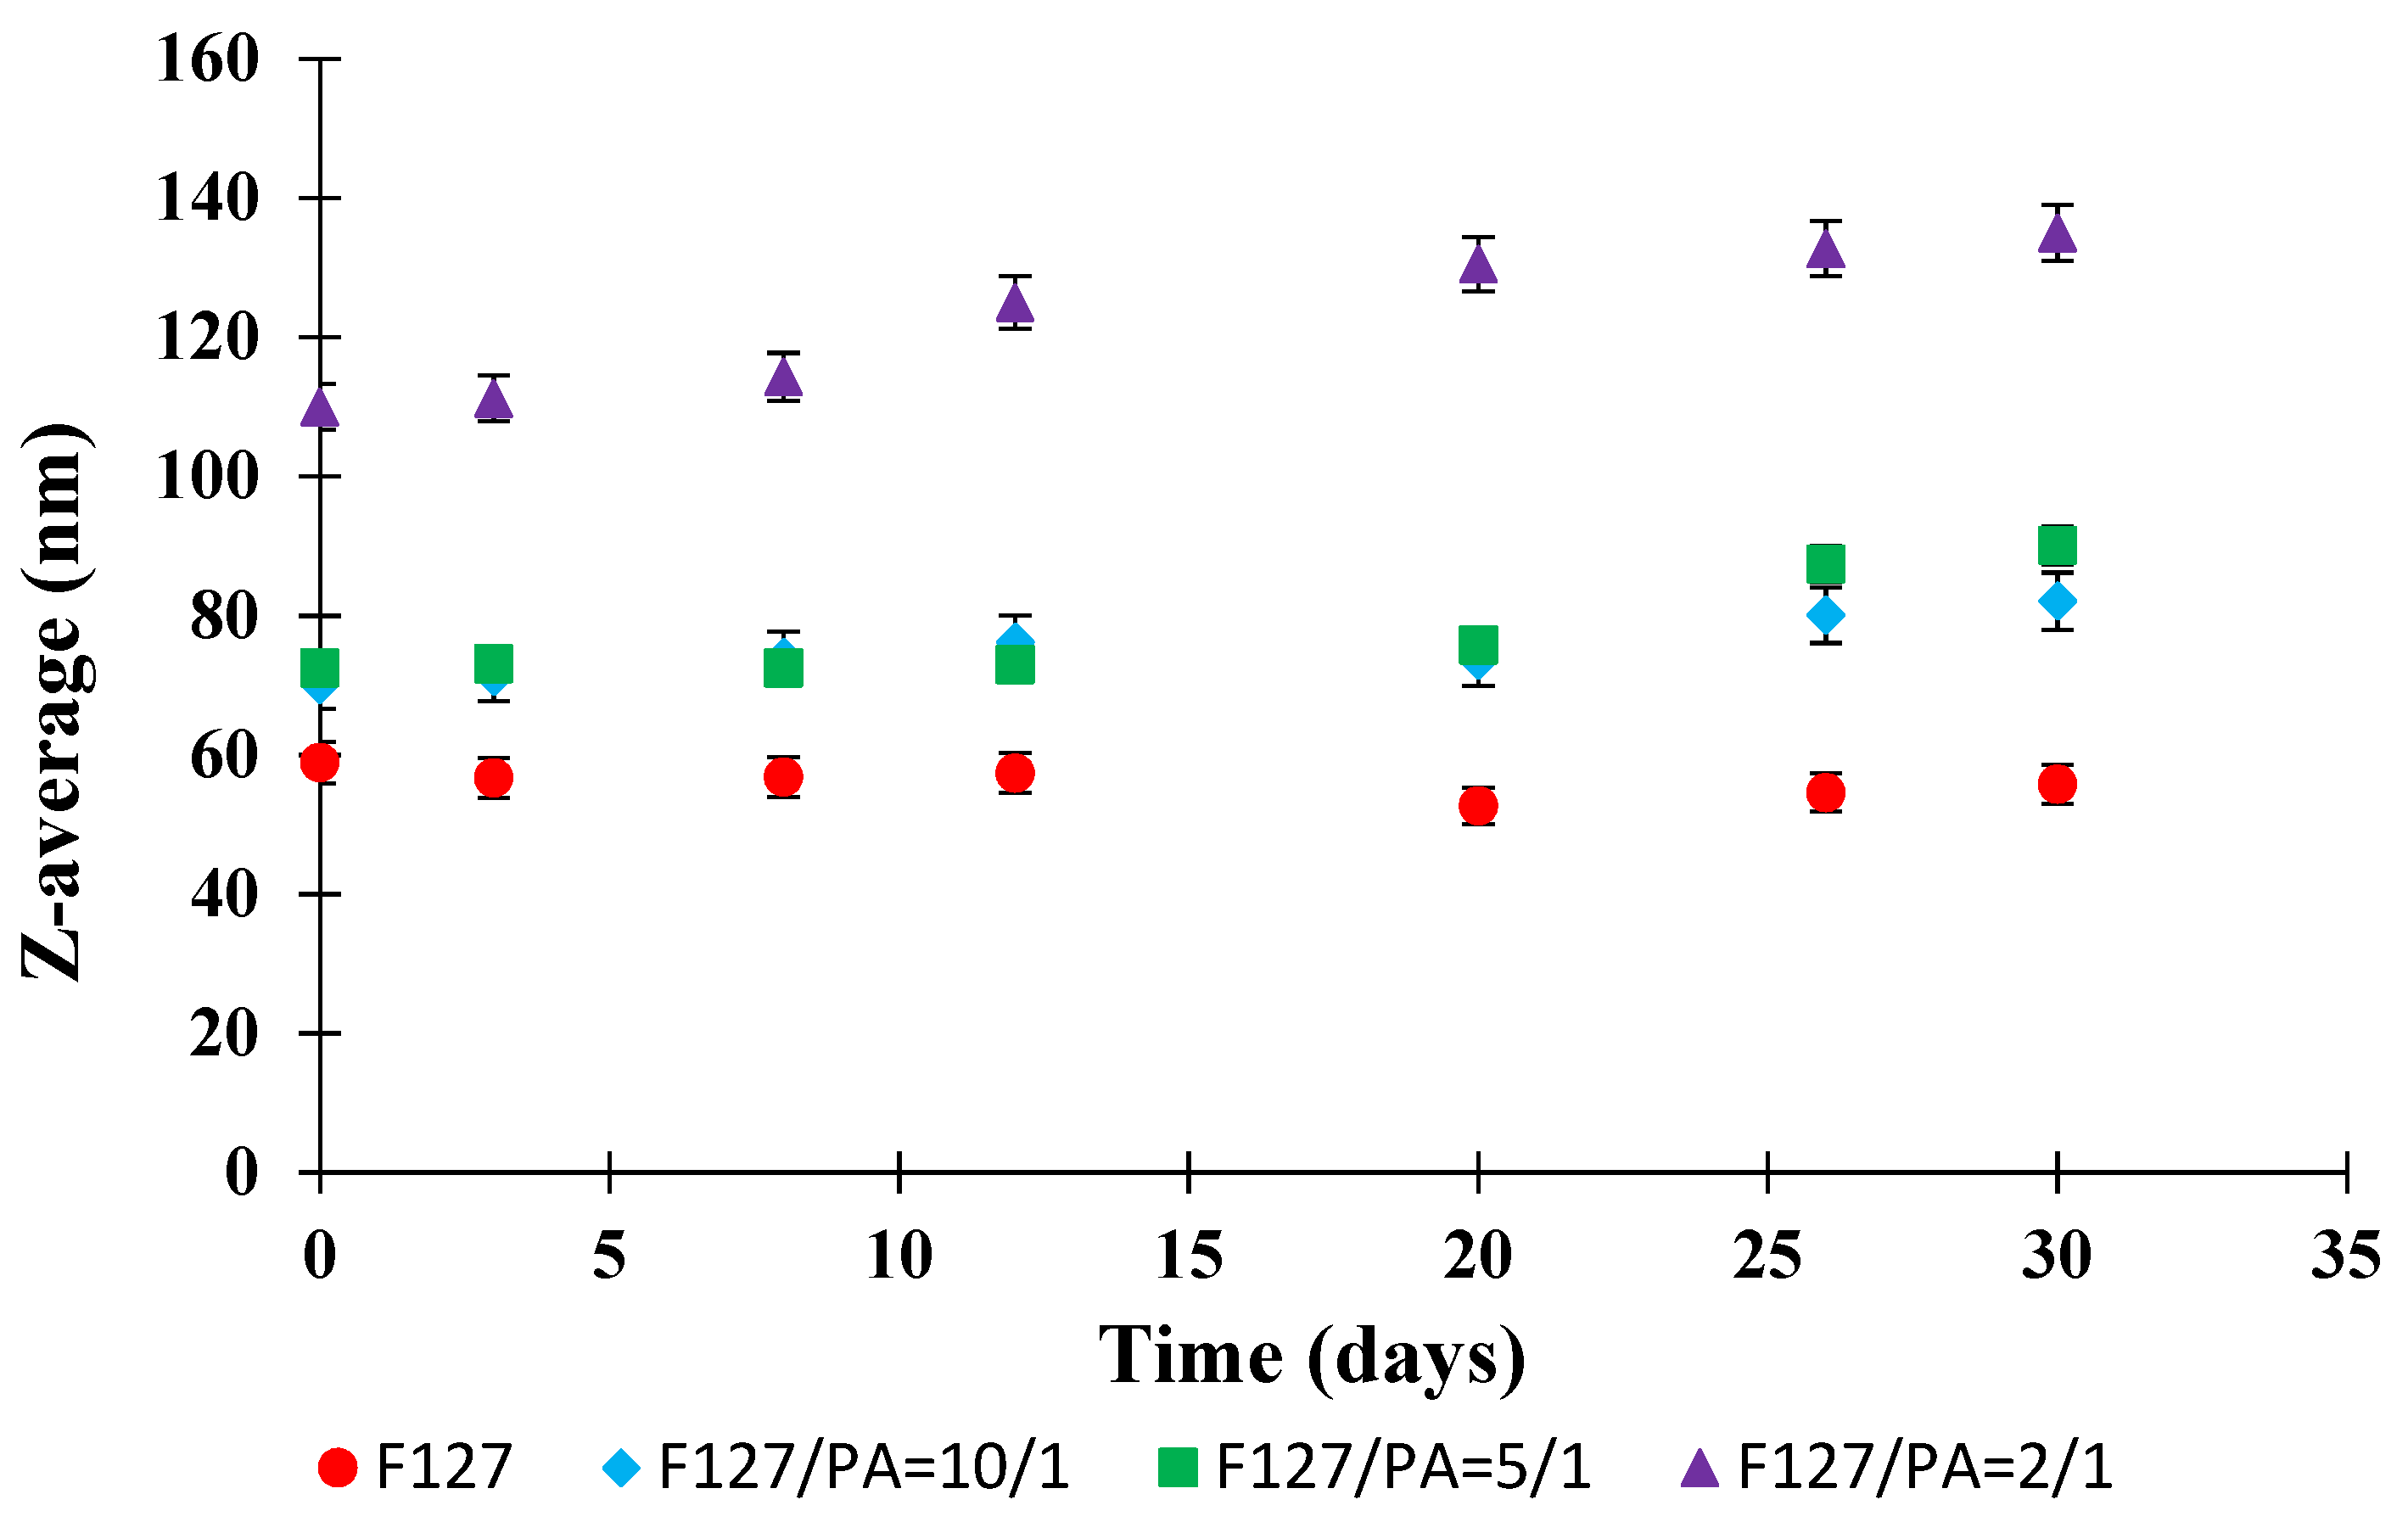

3.1. Micellar Sizes and Stability